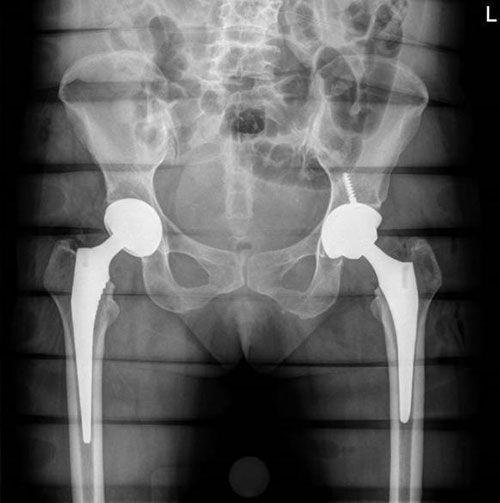

患者术后X线,左侧为机器人辅助下完成的全髋关节置换术

术后,患者对手术效果十分满意。术后影像学结果显示,假体大小、位置、角度、肢体长度、偏心距精准匹配。术后第一天,患者在专科护士的指导下下床活动。